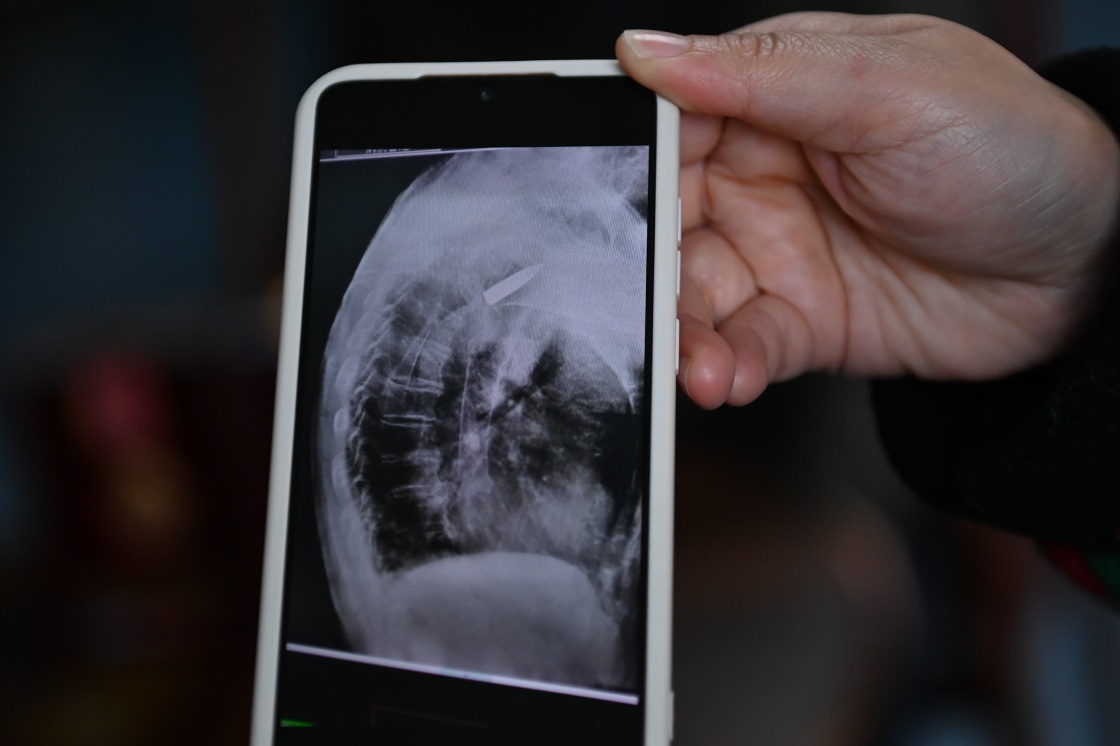

2022年11月11日上午,浙江省平湖市第一人民醫院,消化科內鏡室主任醫師王明友正在為一位吞咽困難的96歲老人做食道支架置入手術(shù)。突然,醫生的眉頭緊皺起來(lái):在X射線(xiàn)下,發(fā)現老人右側肩膀里居然有一顆長(cháng)約3.5厘米的子彈!

醫院的放射線(xiàn)視覺(jué)指引圖像顯示,羅錦文老人右側肩膀里有一顆長(cháng)約3.5厘米的子彈(3月2日攝)。新華社記者 黃宗治 攝

2022年,平湖市第一人民醫院在給老人做食道支架置入手術(shù)時(shí),X射線(xiàn)下清晰地看到老人肩膀里有顆長(cháng)約3.5厘米的子彈。而這顆子彈,早已與老人的骨頭粘在了一起,無(wú)法取出。